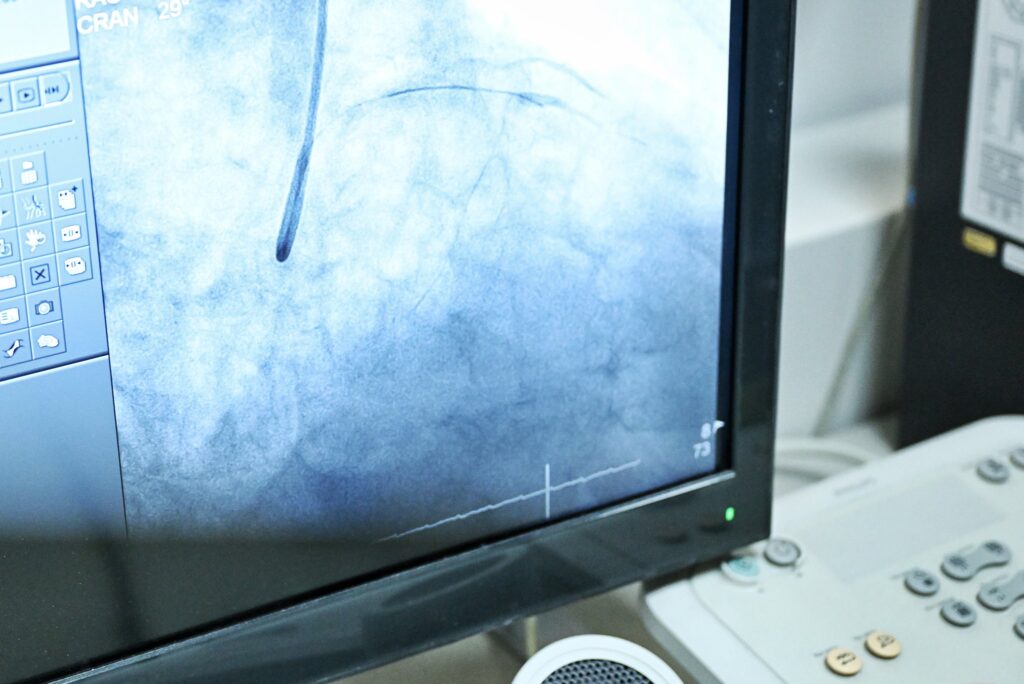

The functionalization of the modern Cath-Lab and the installation of the new angiograph constitute a major step forward in the diagnosis and treatment of cardiovascular diseases.

The investment amounts to approximately 1.5 million euros, while treatment capacities will increase significantly. From over 4,000 interventions per year, as it has been so far, the goals are to reach a capacity of up to 8,000 interventions per year. Of course, we hope that we will not need it, but if we do, we will have the capacity, and in addition, the waiting lists will be reduced.